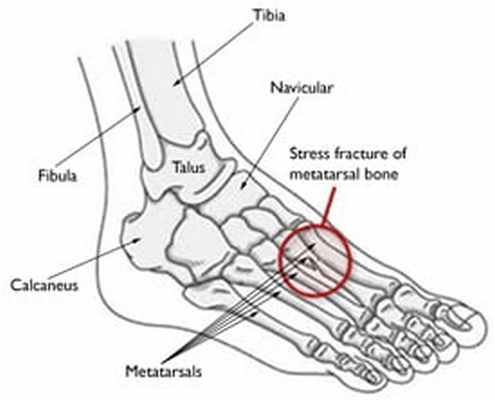

Метатарзалгия - это название боли в области носка, плюсневой кости и передней части стопы. Метатарзалгия и боль в передней части стопы могут быть связаны с несколькими диагнозами, в том числе Неврома Мортона, Hallux Valgus, повреждение груза, стрессовые переломы плюсневых костей, остеоартрит, артрит, подагра, диабетическая невропатия или Болезнь Фрейберга, Вы найдете больше диагнозов, симптомов и тому подобного в нашей статье коллекции боль в ноге, Поскольку существует очень много диагнозов и причин возникновения метатарзалгии, обычно необходимо пройти клиническое обследование у врача, мануального терапевта, физиотерапевта, мануального терапевта и т.п., чтобы выяснить, что вызывает у вас боль.

Рентген может показать, есть ли свободные костные фрагменты или износ стопы или передней части стопы. Один МРТ обследование может показать состояние мягких тканей, ног и сухожилий.